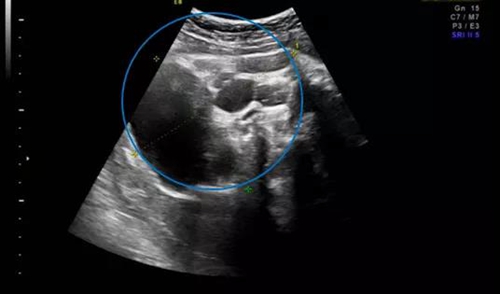

幾個月前,家住外地的準媽媽唐女士(化名)在當地醫(yī)院產檢時,超聲發(fā)現肚里的寶寶患有骶尾部畸胎瘤,直徑達5厘米,近乎胎兒頭顱大小,當地醫(yī)院建議終止妊娠。“二胎放開以來,我和我老公就一直想再要個孩子,好不容易懷上了,我們真舍不得。”唐女士說道。抱著試試看的想法,唐女士被轉診到青島婦兒醫(yī)院胎兒醫(yī)學門診。

在聽到專家們專業(yè)全面的咨詢后,唐女士決定積極配合治療。后期體檢中,寶寶的畸胎瘤逐漸增長,分娩前最后一次超聲提示畸胎瘤直徑達10cm,但并未出現羊水過多等異常情況。